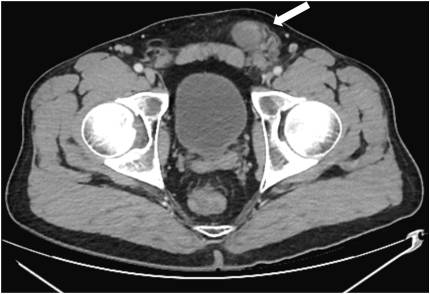

A case of malignant melanoma metastatic to the bladder. Presented with severe anemia secondary to intermittent gross hematuria. Perhaps not as rare as a glance at the literature may suggest! @FoleyAndFollies tinyurl.com/5mjumnrb